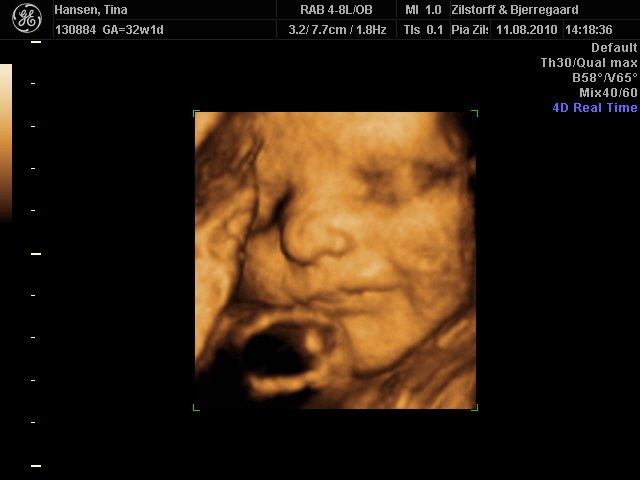

Ihh skøøn bebs. er det ikk os til 3D man sådan kan se hvem bebs ville ligne? ..

Til gennemscanningen gættede de på at vi ventede en pige, men hun lå så dumt så vi tog en 3D for ensikkerheds skyld så vi ikke stod med lyserødt tøj til en dreng